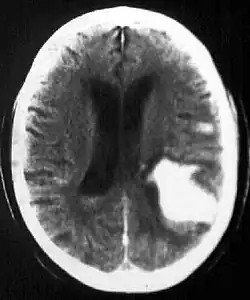

Diagnosis

Computed tomography (CT scan): A CT scan may be normal if it is done soon after the onset of symptoms. A CT scan is the best test to look for bleeding in or around your brain. In some hospitals, a perfusion CT scan may be done to see where the blood is flowing and not flowing in your brain.

In the elderly population, amyloid angiopathy is associated with cerebral infarcts as well as hemorrhage in superficial locations, rather than deep white matter or basal ganglia. These are usually described as "lobar". These bleedings are not associated with systemic amyloidosis.